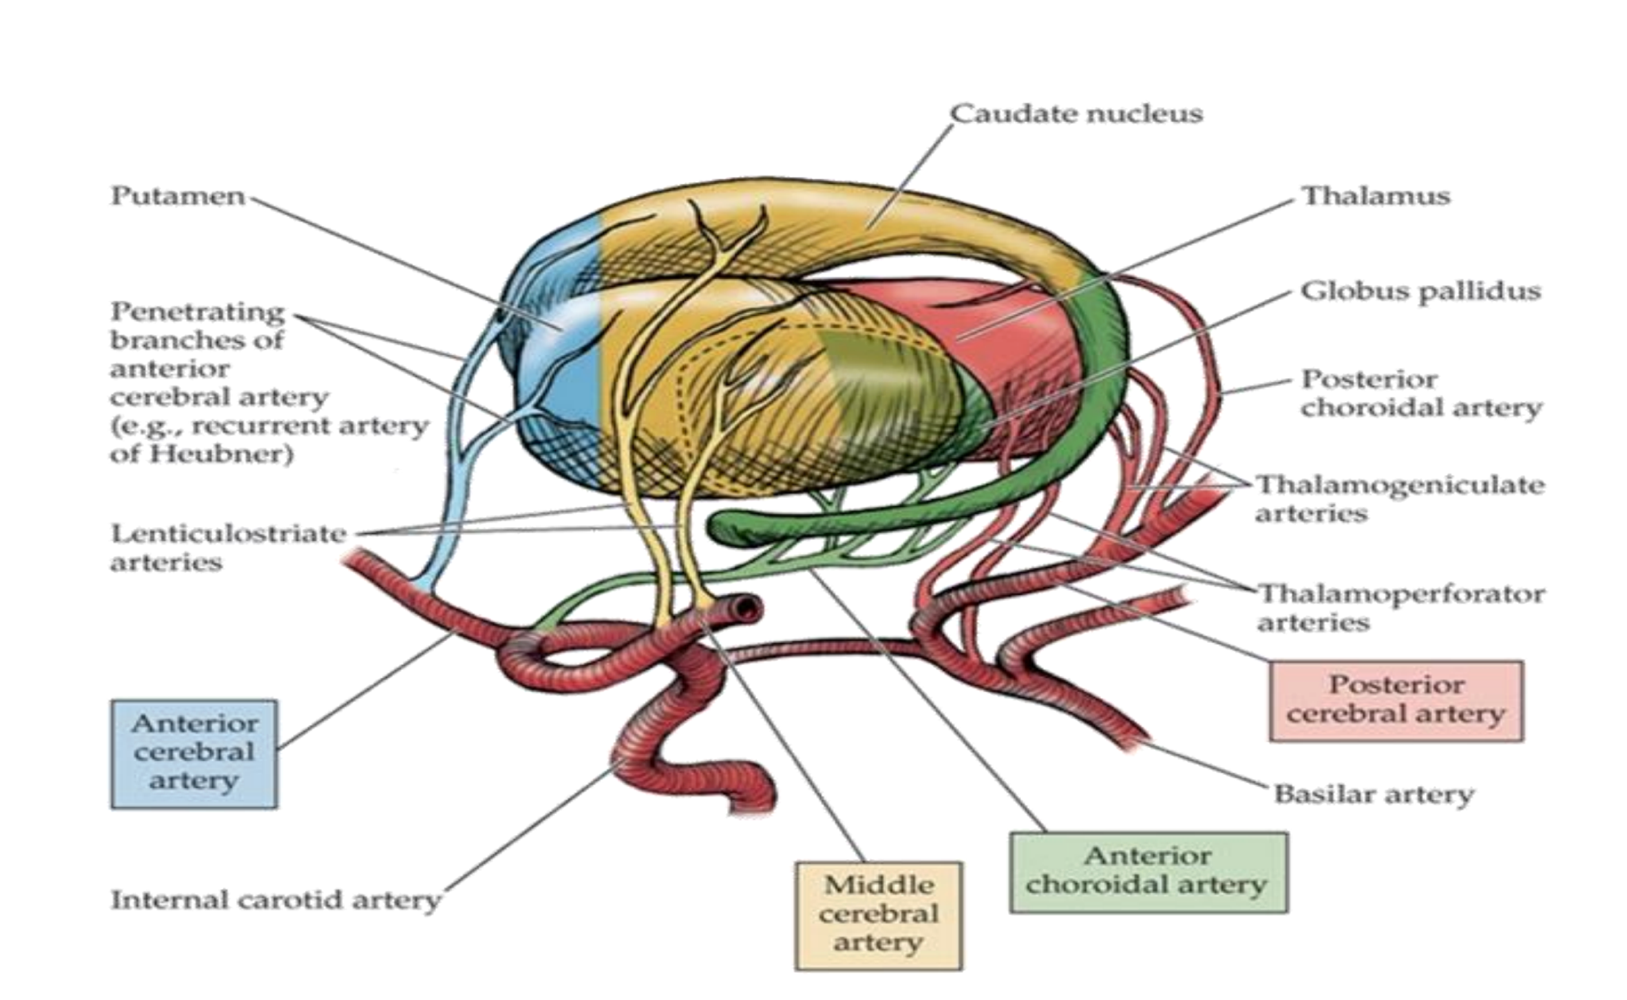

What supplies blood to the caudate nucleus?

Branches from anterior cerebral artery (anterior part)

Boddy of the middle cerebral artery

Tail of the anterior choroidal artery.

What supplies blood to the putamen?

Middle cerebral artery

Branches from anterior cerebral artery (anterior part)

What supplies blood to the globus pallidus?

Lenticular striate arteries

Anterior choroidal of internal carotid & internal capsule

What supplies blood to the thalamus?

Lenticulostriate arteries from the middle cerebral artery